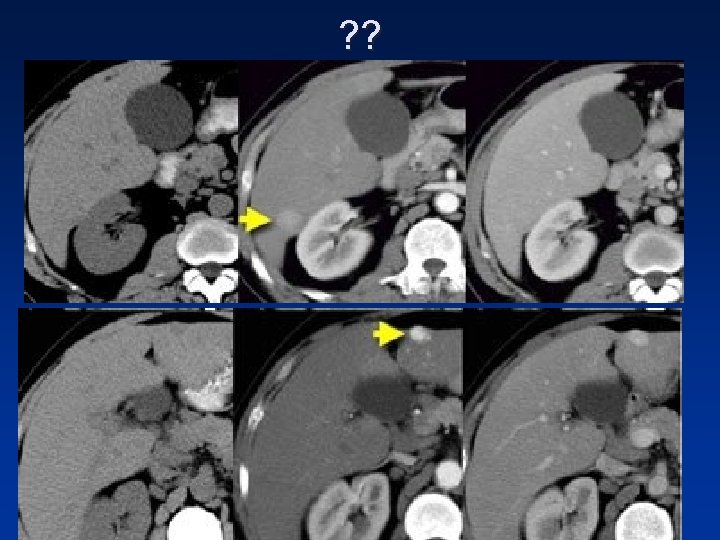

• In the arterial phase we see two hypervascular lesions. Now do not just concentrate on the images, where you see the lesions best. You have to look at all the other images, because they give you the clue to the diagnosis. The upper images show a lesion that is isodens to the liver on the NECT. In the arterial phase there is enhancement, but not as dense as the bloodpool. In the portal venous phase the lesion is again isodense to the surrounding liver parenchyma and you can't see it. If you only had the portal venous phase you surely would miss this lesion. The lower images show a lesion that is visible on all images. You see it on the NECT and you could say it is hypodens compared to the liver. Does this help you? No, not in the least. However if you look at the bloodpool, you will notice that on all phases it is as dense as the bloodpool. So we have a HCC in the right lobe on the upper images and a hemangioma in the left lobe on the lower images. The key is to look at all the phases.